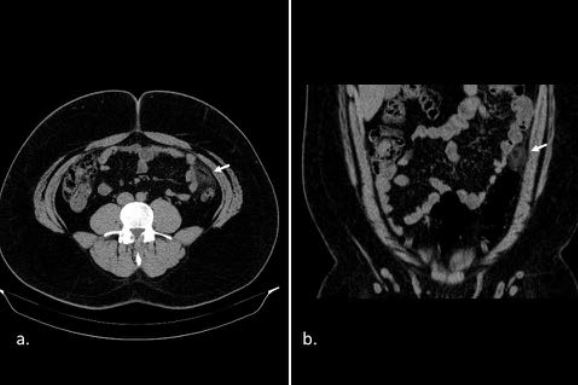

Estudio por imagen de la patología mesentérica y peritoneal

Jorge Antonio Nogales Montero, Yonil Gregorio Piña Alcántara, Rocio Mora Monago, Ana López Moreno, Jose Pedro Mora Encinas, Beatriz Martin Martin